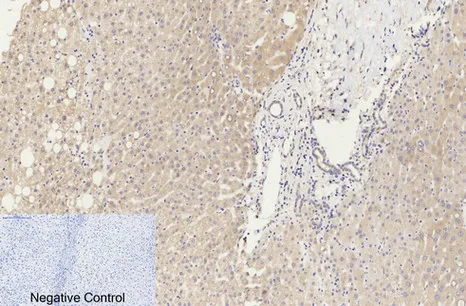

Cleaved-Caspase-9 p35 (D315) Rabbit Polyclonal Antibody

Cat: APRab08971